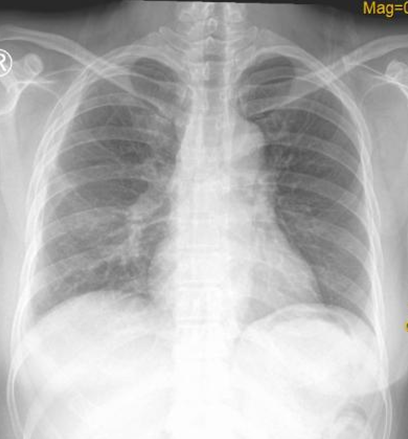

术后,小林转入普通病房观察,在胸外科医护密切观察及治疗下,小林恢复十分顺利,已于近日顺利出院。

术后顺利拔除引流管,复查胸片理想